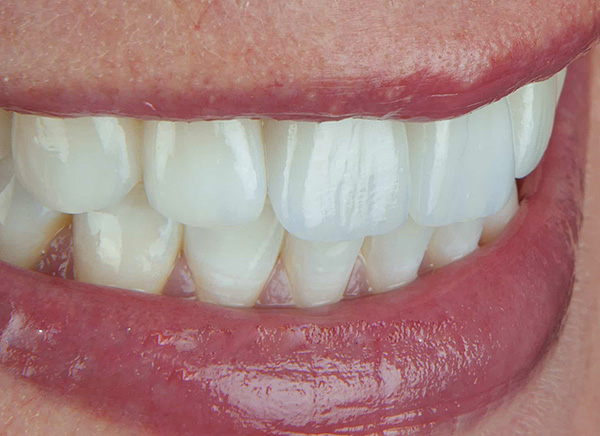

- Le corone in zirconia sono le più costose, ma anche le più resistenti e vantaggiose in termini di estetica. Possono durare più di 20 anni senza problemi. Ideale per il restauro dei denti anteriori, perché, a differenza dei cermet, non hanno una base scura. Ma l'elaborazione della zirconia richiede attrezzature speciali (le corone sono create dalla simulazione al computer e dalla successiva fresatura robotizzata), quindi il loro costo è elevato.

Le corone di zirconia sono mostrate nella foto sotto: